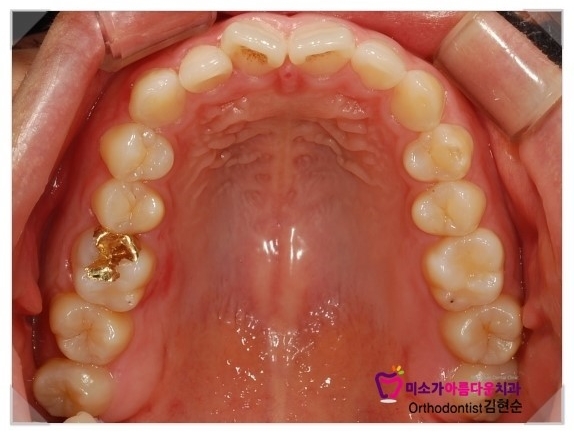

아랫니가 거의 없는 것 같아서 너무 고민이라고

하셔서 이번에 교정으로 치열이 다시 정렬이 끝난 사진입니다.

치아 안쪽에 철사처럼 보이는 것은 교정이 끝나고 붙이는 교정 유지장치입니다.

교정후 교정유지장치를 하지 않으면 치아가 원상태로 돌아가기때문에 교정한 기간만큰 꼭 해주어야 합니다.